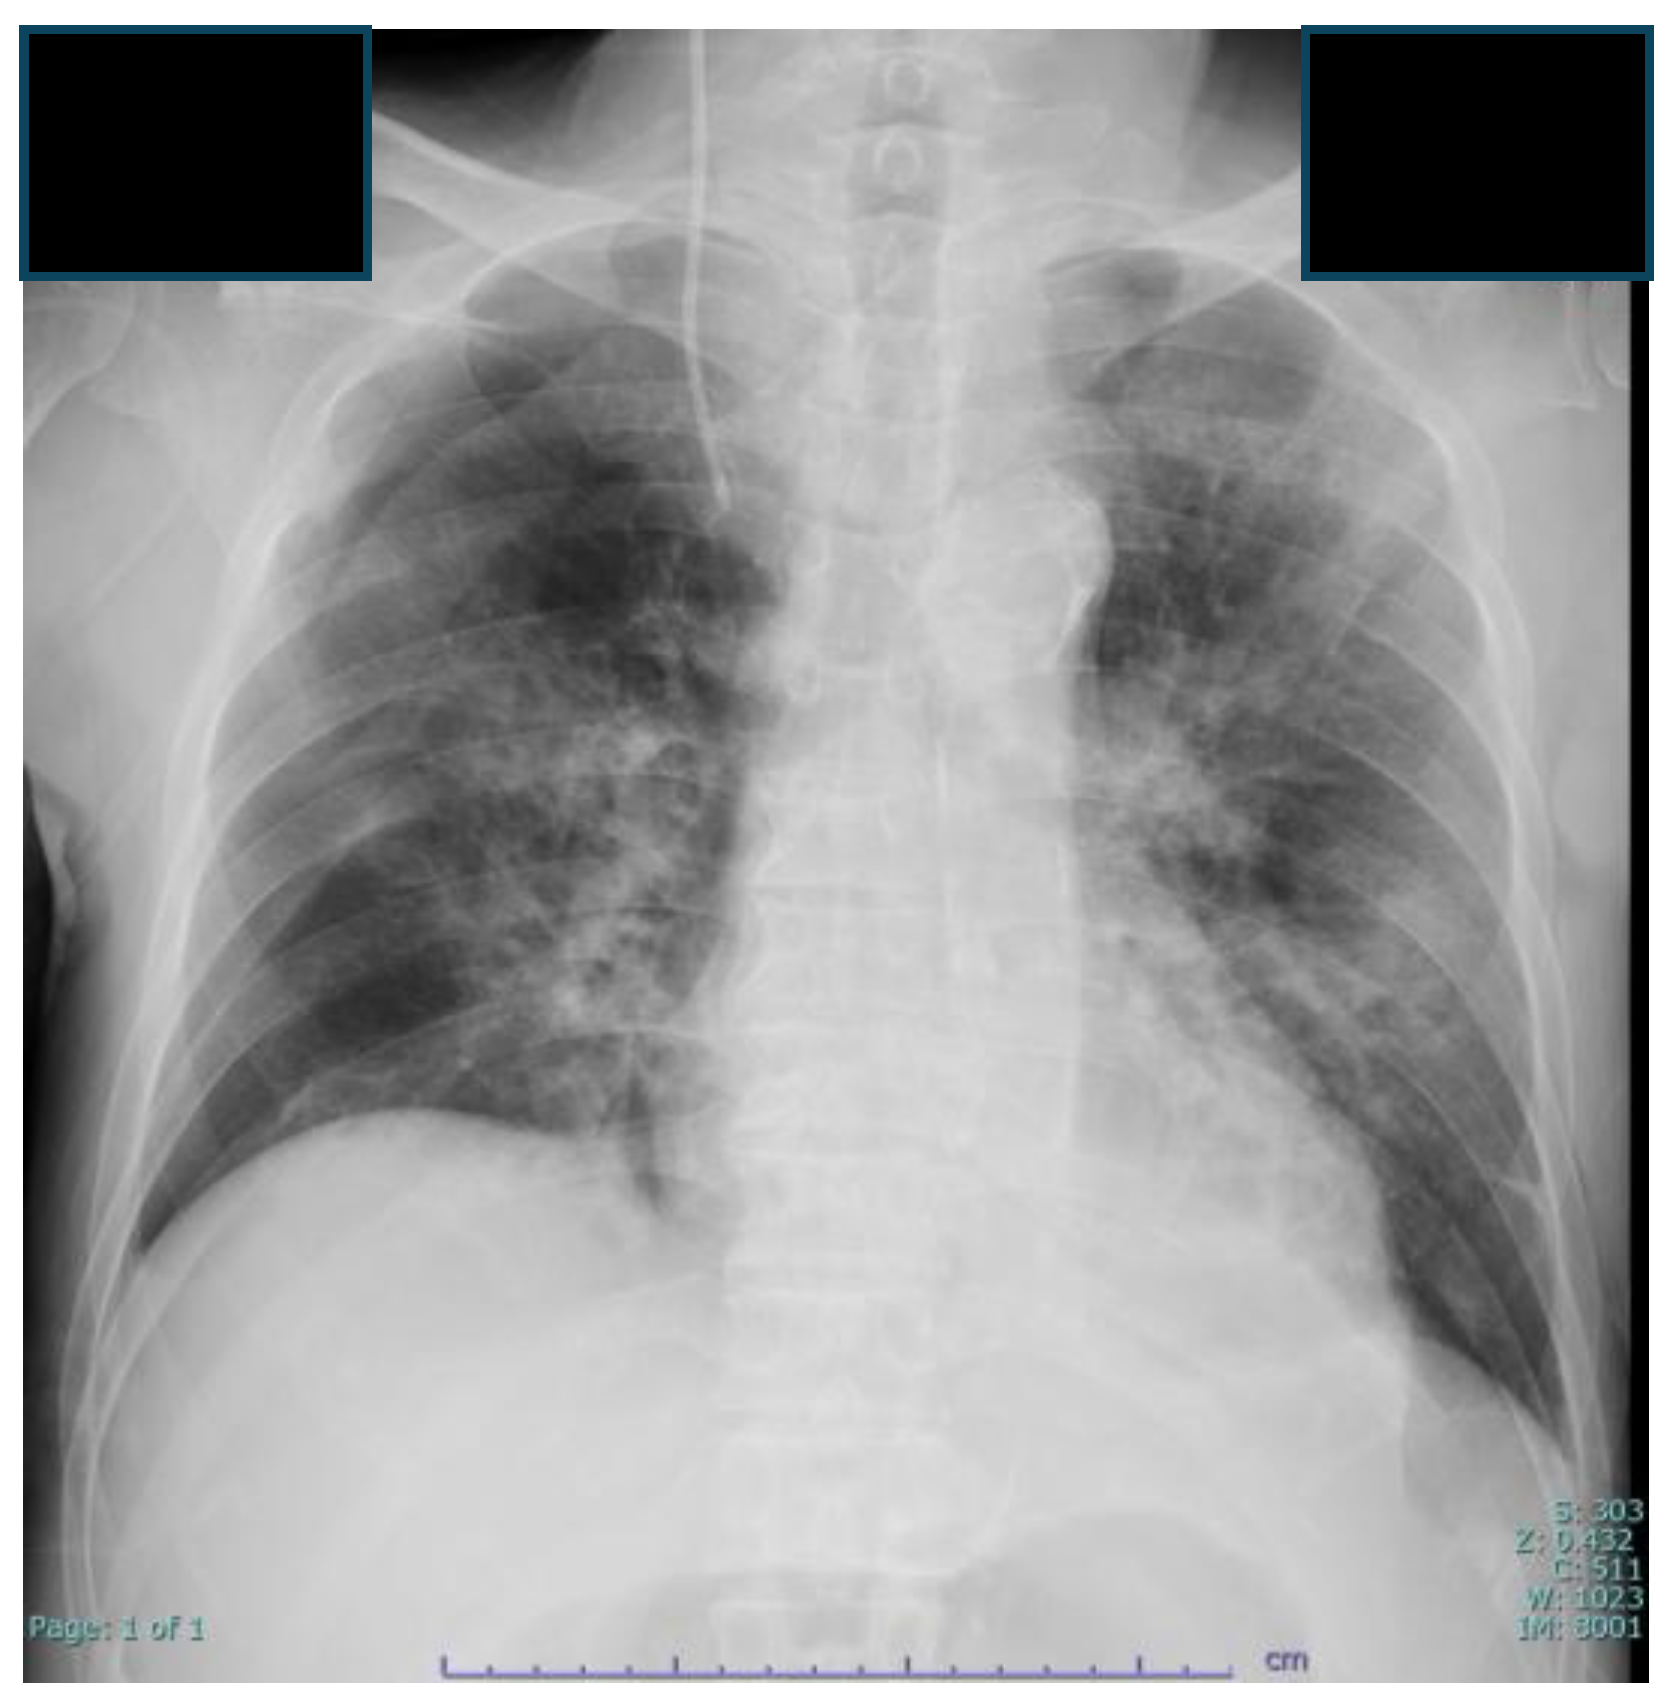

2.4. Laboratory and Imaging Findings

3. Clinical Course and Management (Figure 2)